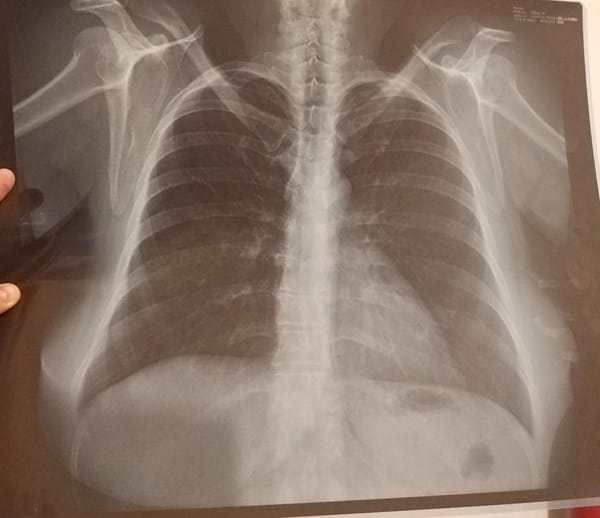

¿Que enfermedad puedo tener con esta radiografía?

Mi familiar tiene 49 años, es mujer, nunca ha fumado, pero tiene presión en el pecho, falta de aire, dolor en el lado derecho de la espalda, y cansancio... El doctor le mando a hacer una radiografía y no le ha dicho que tiene... ¿qué puede ser? Ayuda, ella se siente muy mal